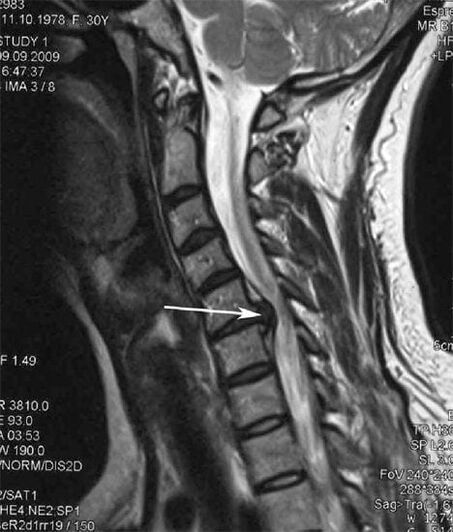

In the early stages, osteochondrosis is detected using MRI.Then, the pathology can be diagnosed using radiography.On radiographs of the cervical spine, a decrease in the distance between the vertebrae, pathological changes in the facet joints, and osteophytosis become apparent.

Many people complain that they cannot turn their neck because of the severe pain that appears after suddenly lifting something heavy.This phenomenon indicates the formation of a herniated disc.The cause of pain in the back, neck and upper limbs pinches one of the nerve roots emerging from the spinal cord.

| Cervical osteochondrosis | The appearance of pathological changes in one or more segments of spinal motion.Impaired spinal mobility, development of myofascial pain syndrome and spinal root pinching | Pain, paresthesia and motor disturbances in the cervical region, which spread to the back of the head and upper limbs.Detection of characteristic changes in the spine on MRI and radiography (osteophytes, decreased distance between vertebrae, signs of damage to intervertebral joints) |